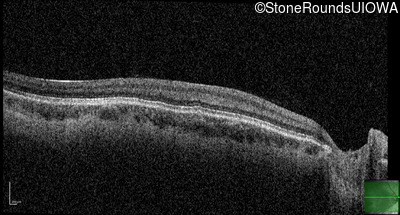

Optical Coherence Tomography - Right - 20/160 +1

Exemplar / OCT Stack

OCT Stack